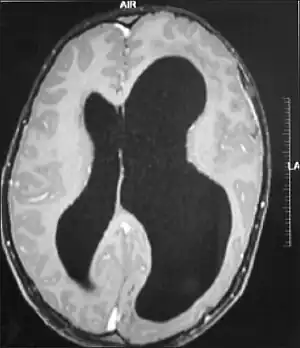

| An MRI of a patient with benign familial macrocephaly (male with head circumference > 60 cm) | |

Macrocephaly is a condition in which circumference of the human head is abnormally large.[1] It may be pathological or harmless, and can be a familial genetic characteristic. People diagnosed with macrocephaly will receive further medical tests to determine whether the syndrome is accompanied by particular disorders. Those with benign or familial macrocephaly are considered to have megalencephaly.